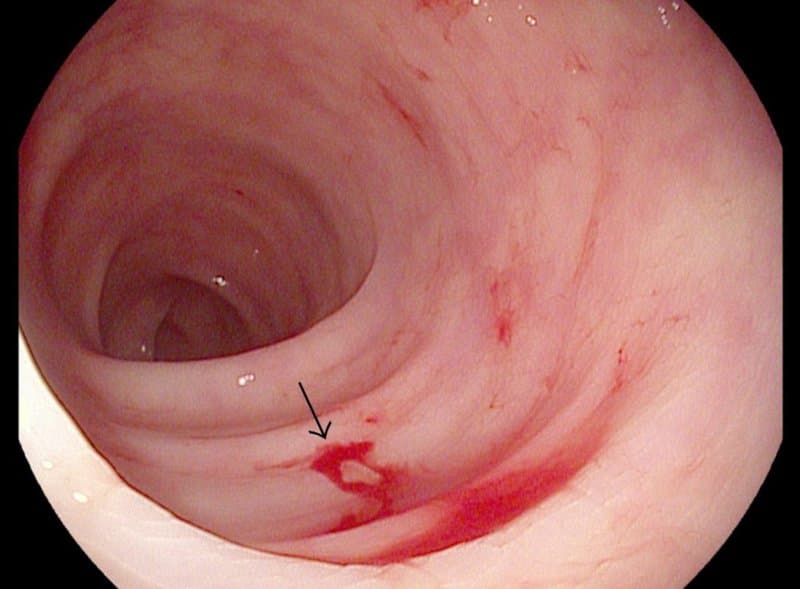

- Chảy máu trong ổ bụng gây đau bụng hoặc sưng, chướng vùng bụng tại chỗ có cơ quan xuất huyết.